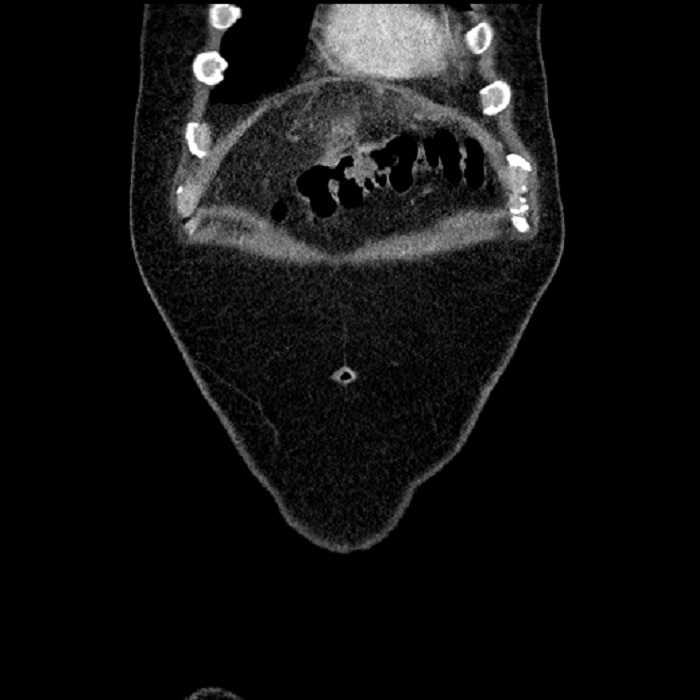

Age: 63

Sex: Male

Indication: Abdominal pain

• Large fluid density structure in hepatic segments 7 and 8 measuring 10 x 7 x 7 cm with internal septation and circumferential ill-defined low density compatible with edema

• Peripherally enhancing subcapsular collections along the anterior margin of the left hepatic lobe measuring 3 x 1 cm and 2 x 1 cm

• Clearly marginated fluid density structure in segment 7 and several other scattered tiny hypodensities, which likely represent cysts

Acute sigmoid diverticulitis complicated by a small contained perforation and a large abscess in the right hepatic lobe. Additional small subcapsular abscesses along the anterior margin of the left hepatic lobe.

Hepatic abscess showing the double target sign with low density internally surrounded by a thin inner enhancing rim (red arrow) and ill-defined outer low density rim (yellow arrow). Blue arrow indicates an internal septation. Red arrows: additional smaller subcapsular abscesses. Red arrow: focal contained perforation associated with diverticulitis.